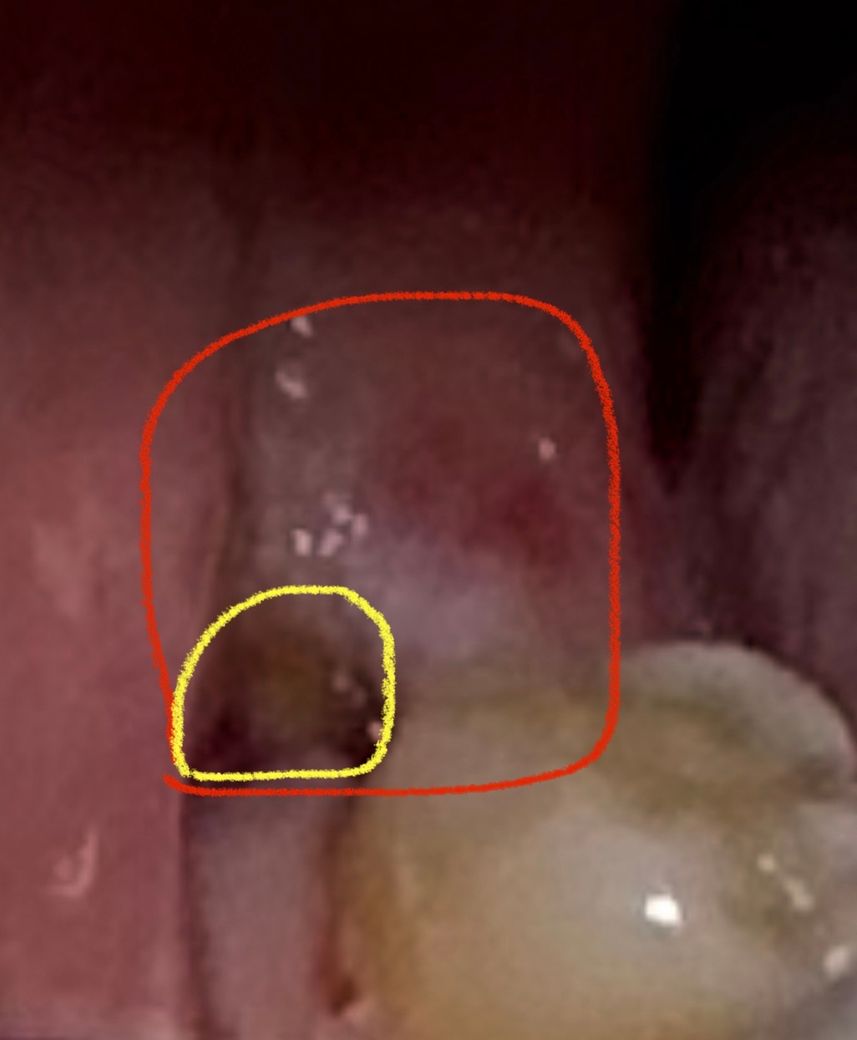

사랑니 발치후 잇몸 구멍이 났습니다.

사랑니 발치후 72시간째입니다.

발치 자리에 잇몸이 70%가량 새로 덮어진 상태(사진의 빨간영역)이고,

사진의 노란색 자리는 구멍이 보이고 있습니다.

• 1번 째 사진

사진상으로 발치한곳은 잘 아물고 잇는거 같습니다. 잇몸이 치유되는 과정주엥 생기는 자연스러운 현상이니 너무 걱정하지마세요.

염증의 소견은 보이지 않습니다. 정상적으로 잘 낫고 있어보이니 며칠정도 관리잘해주시면 됩니다.

발치 후 3일째의 적절한 치유 양상을 보여주고 있습니다 걱정마시고 발치 후 주의사항 잘 지키세요

이정도면 정상적으로 아물고 있는 것으로 보입니다. 시간이 지나면 점점 살이 차오르게 됩니다. 건드리지 말고 그냥두면 됩니다.

사랑니를 발치하고 나면 발치한 부위에 구멍이 날수 있습니다. 이런 부분은 시간이 지나면서 점차 차오르게 됩니다. 발치한부위에 이물질이 들어가게 되면 가볍게 가글을 해주는 것이 좋습니다.

억지로 제거를 하려고 하지 않는것이 좋습니다.